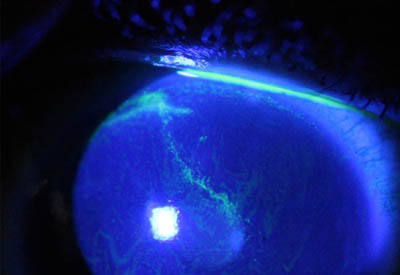

Perineuritis

No tienen los bulbos terminales de las dendritas del Herpes Simple

Formación de lineas epiteliales elevadas que pueden dar la imagen de Seudodendrítas

Queratitis Perineuritis Dendritas Herpéticas

Formación de lineas epiteliales elevadas que pueden dar la imagen de Seudodendrítas + Perineuritis

El cuadro clínico inicial progresa, aparecen infiltrados estromales anteriores focales o difusos, edema circunscrito y a veces perineuritis